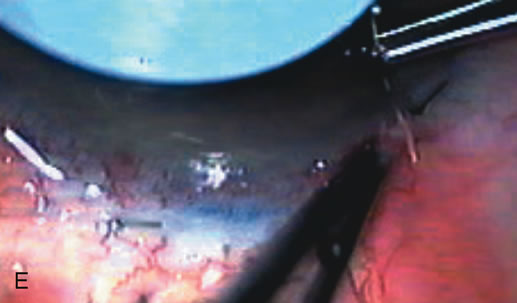

Nonpenetrating procedures as they exist today generally decrease postoperative complications but do not reduce IOP as successfully as trabeculectomy.140 The success rate also appears to be highly dependent on race, length of topical antiglaucoma therapy, and prior ocular surgery.141,142 Deep sclerectomy combined with phacoemulsification results in an IOP reduction similar to phacotrabeculectomy at one year with comparable visual outcome.143 Phacoviscocanalostomy lowers IOP by approximately 33%144 through either a one- or two-site approach145 (Fig. 4). Nonpenetrating procedures are in evolution, and their place in long-term glaucoma care is still unclear.

Fig. 4. Viscocanalostomy with deep sclerectomy and phacoemulsification. Nonpenetrating filtration procedures (NPFS) may be combined with phacoemulsification. Patients with mild disc damage and a history of limited topical drug therapy are the best candidates. Patients who require an IOP in the low teens are not good candidates for NPFS. By definition, NPFS is designed to lower IOP without penetrating into the anterior chamber, thereby avoiding the complications associated with trabeculectomy. Viscocanalostomy is intended to allow aqueous to percolate through a trabeculodescemetic membrane into a subscleral cavern created by the deep sclerectomy. The aqueous diffuses from the cavern into the dilated ostia of Schlemm's canal and into the episcleral venous plexus. A. Fashion a uniform 300-micron superficial scleral flap 1 mm into clear cornea. B. Construct a second 600-micron deep flap that facilitates the unroofing of Schlemm's canal, seen as the darker area. C. Use viscoelastic to dilate the ostia of Schlemm's canal. The major problem with viscocanalostomy is the eventual closure of the ostium decreasing flow to the episcleral plexus. D. Dissect the deep flap anteriorly into clear cornea creating the trabeculodescemetic membrane. This membrane is clearly seen between the scleral spur and the bend of the deep flap. The integrity of this membrane ensures the nonpenetrating portion of the surgery. Another problem with NPFS is the eventual fibrosis of this initially transparent membrane requiring goniopuncture. E. Deep sclerectomy gets its name from removal of the deep flap. Removal of this flap creates the potential subscleral space for accumulation of aqueous before it enters Schlemm's canal and exits the episcleral venous plexus. After removal of the deep flap, the superficial flap is sutured into place and conjunctiva closed. Approximately half of these procedures develop a shallow bleb.